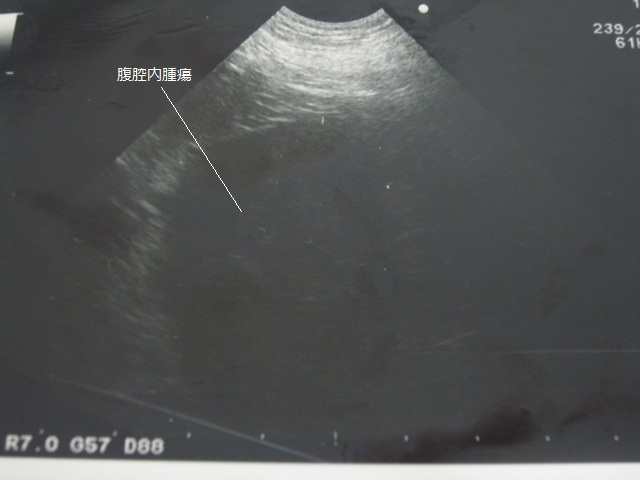

エコー画像です。

脾臓あたりに大きな腫瘤を認めました。